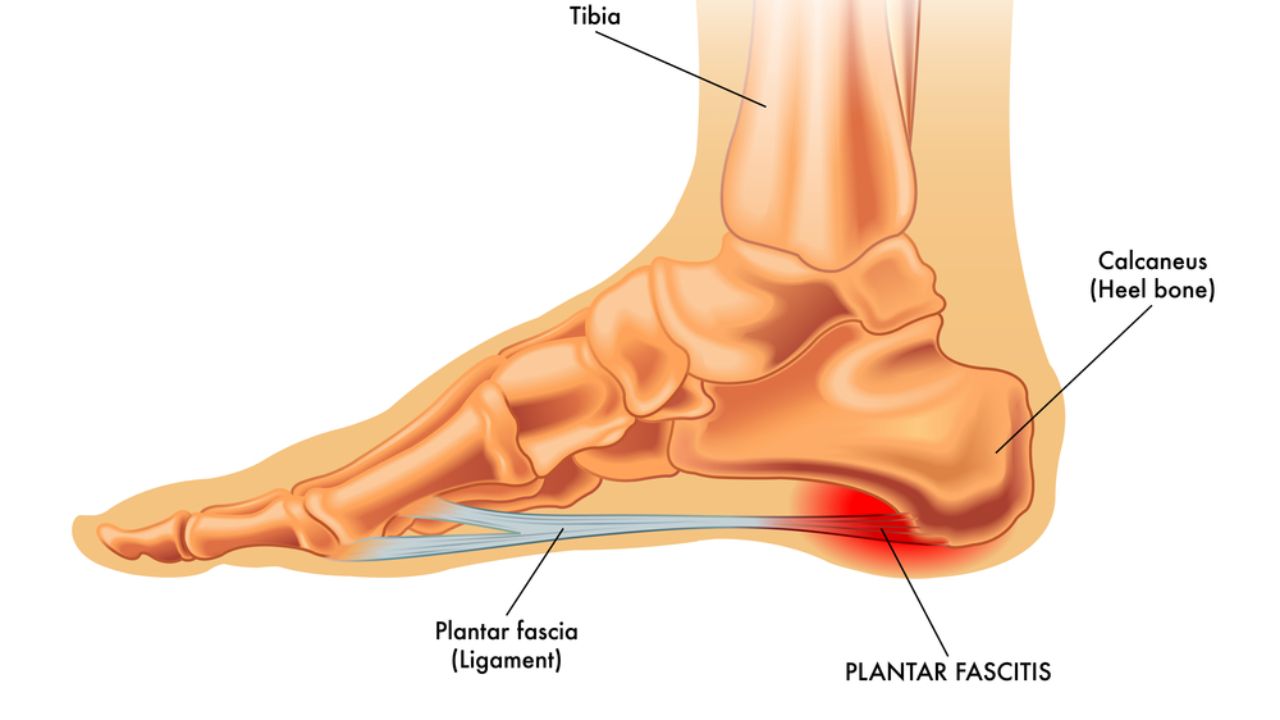

Fascite Plantar Agendar consulta Aquela dor aguda no calcanhar, especialmente nos primeiros passos do dia, é um incômodo que afeta muitas pessoas e tem nome: